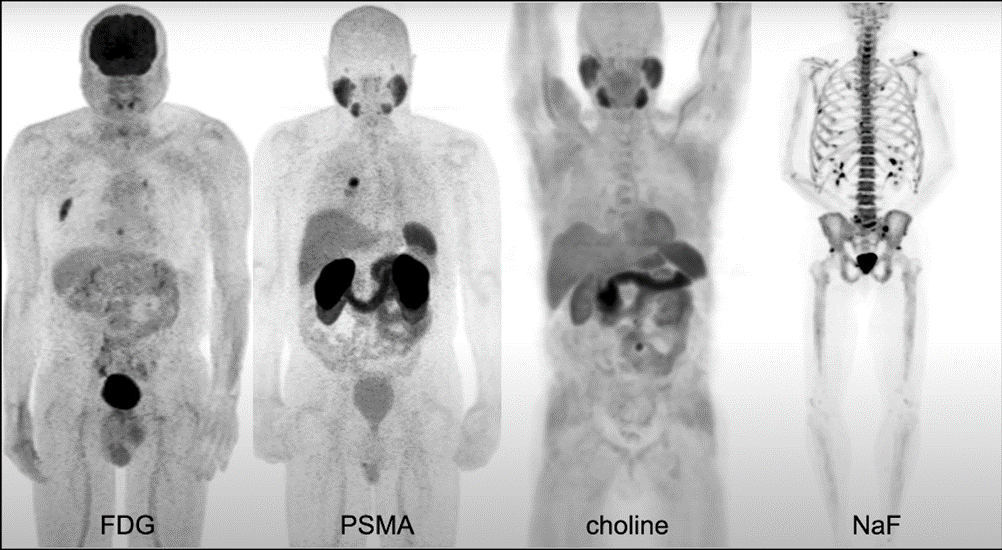

How Is PSMA PET Imaging Different from Current Prostate Cancer Imaging?

Traditional imaging methods primarily evaluate structural abnormalities.

Conventional Imaging Limitations

| Imaging Type | Primary Limitation |

| CT Scan | Limited sensitivity for small metastases |

| Bone Scan | Lower specificity |

| MRI | Primarily anatomical evaluation |

| Conventional PET | Less prostate-specific targeting |

PSMA PET Imaging Advantages

| Feature | PSMA PET Scan |

| Molecular targeting | Yes |

| Detects low-volume disease | Higher sensitivity |

| Detects recurrence at low PSA | Yes |

| Micro-metastatic detection | Improved |

| Treatment planning support | Strong |